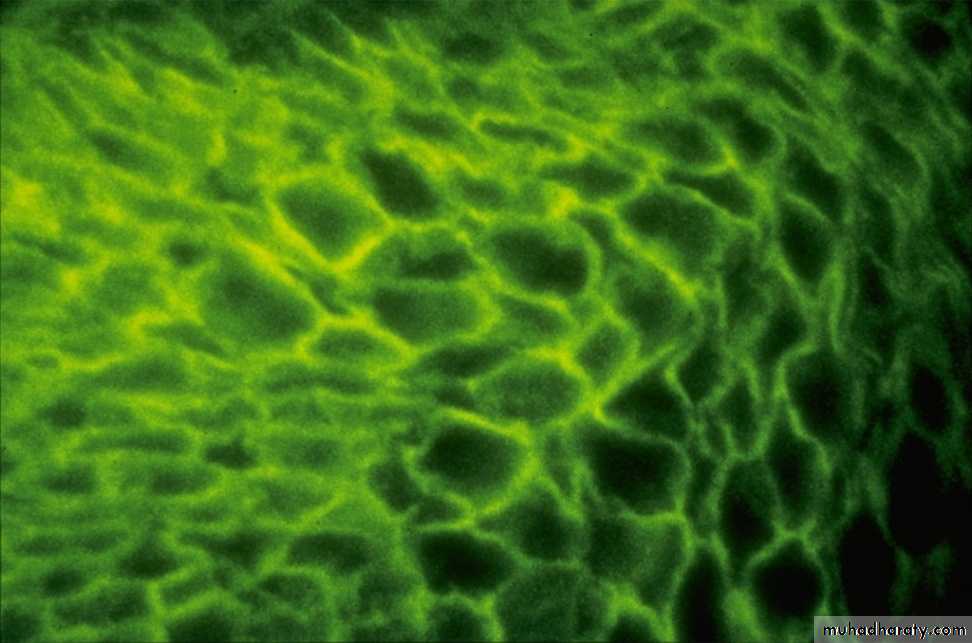

Investigations• DIF Technique:

• A peri-lesional skin from the patient is stained with a fluorescen-labeled Anti-IgG and Anti-C3 Abs to detect tissue fixed autoantibodies. It shows IgG and C3 deposition in epidermal intercellular spaces around the keratinocytes i.e. Desmosomal Antibodies.

• Indirect Immunoflourescence Technique:

• IgG anti-Desmosomal Abs can be detected in the serum of about 90% of patients with P. vulgaris.

• Technique: Incubate Patient’s serum with monkey’s esophageal mucosa and then stain it with a fluorescen-labeled Anti-IgG. Positive test shows IgG deposition in epidermal intercellular spaces around the keratinocytes i.e. Desmosomal Antibodies. This technique:

• Is useful in detecting circulating autoantibodies.

• Can be used to measure disease activity in P. vulgaris (through measuring Ab titer by serial dilution of the patient serum). It is useful in the follow-up of patient on corticosteroid therapy as the Ab titer correlates with the disease activity in patients with P. vulgaris.